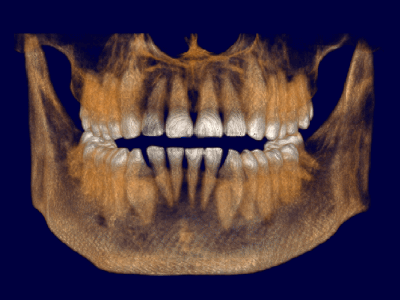

Pro Patient: Our state-of-the-art cone-beam computed tomography (CBCT) technology could selectively image the sinus, oral maxillofacial, para-nasal sinuses, ear & throat regions.

Proactive Dental Management thru our 3D Imaging Manipulation Software

With Oral Maxillofacial CT Scans, your dentist enhances his ability to proactively manage your health concern thru accurate diagnosis & better treatment planning. Moreover, the patient benefits from a painless,low radiation dose CT Scan procedure.